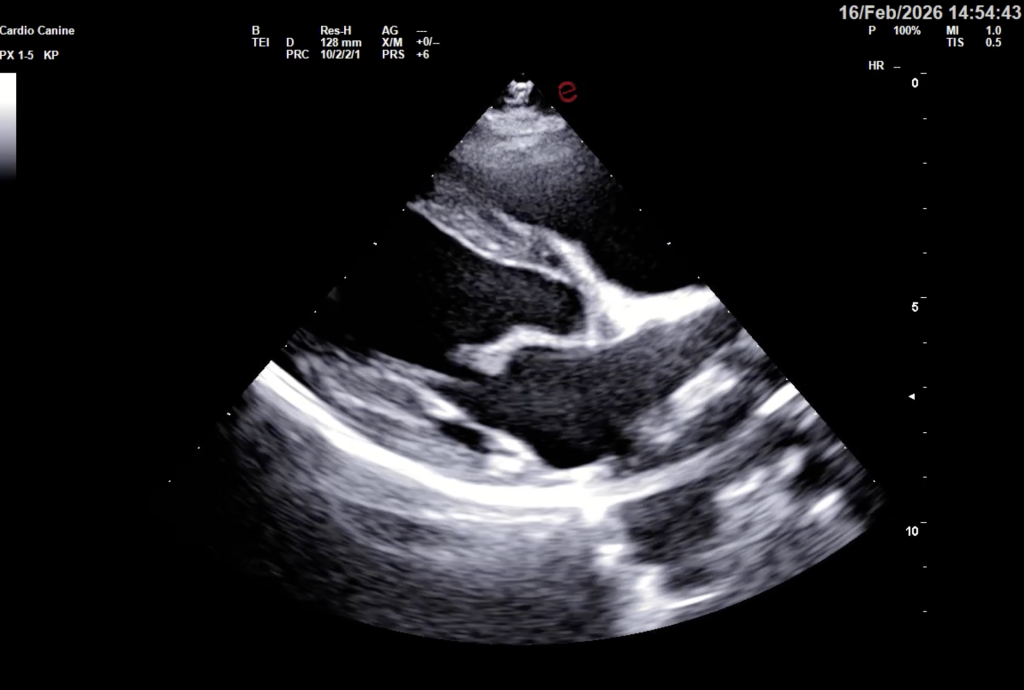

Aby precyzyjnie ocenić ukryte funkcje serca, nowoczesna kardiologia wykorzystuje między innymi wysokiej klasy aparaty ultrasonograficzne. Pozwalają one lekarzowi nie tylko na żywo obserwować pracę zastawek, ale też mapować przepływ krwi i mierzyć grubość ścian mięśnia sercowego z dokładnością do ułamków milimetra – i to wszystko całkowicie bezboleśnie dla zwierzaka.

- Echokardiografię (USG serca): Złoty standard w kardiologii. Pozwala na bezbolesne „zajrzenie” do wnętrza bijącego serca w czasie rzeczywistym, ocenę pracy zastawek i grubości ścian mięśnia sercowego.